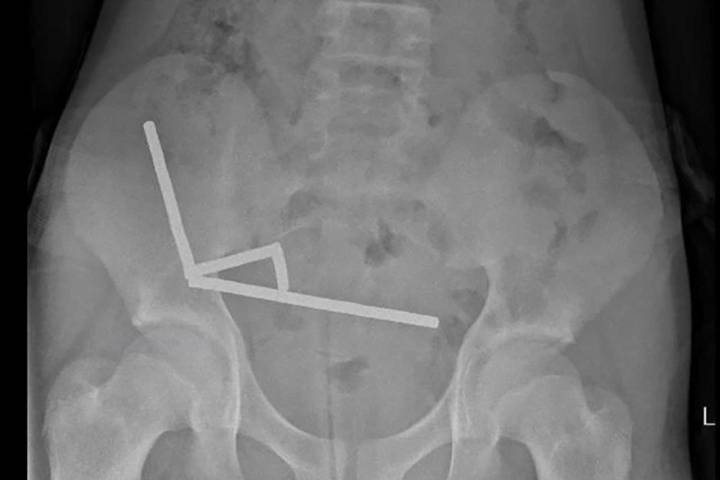

Researchers said an X-ray was taken and showed “four linear chains of magnets” linked together, composed of what the boy indicated was “approximately 80–100 5x2mm high-pow